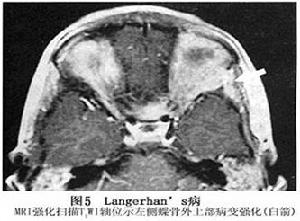

3.CT掃描 眶骨骨質破壞呈溶骨性,邊緣清晰,局部軟組織腫脹可以侵犯眼外肌、淚腺、甚至眼球,顳肌亦可侵犯,增強後CT掃描呈中度到明顯強化。骨破壞常發生在眶前或前顳部,顳鱗部及眶骨骨質破壞均可引起眼球突出。

4.MRI 病變常位於肌錐外,表現為不規則腫塊,病變發展到一定程度可破壞眶壁,侵及顳窩或顱腔侵及顱內者,類似其他顱眶溝通瘤表現,但境界多較清楚,T1加權像呈中低信號,T2加權像呈中高信號。腫塊侵及眼外肌致其受壓移位,境界不清眼球常有突出。